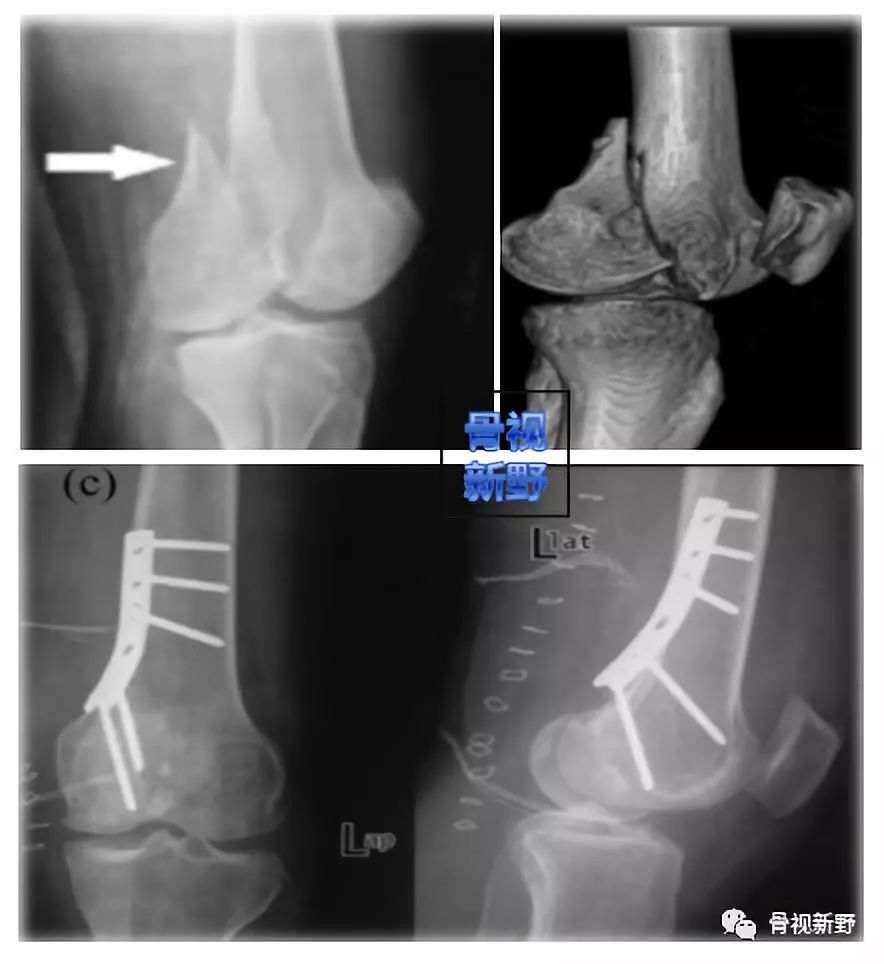

Letenneur II型是完全关节内骨折,骨折线接近后髁关节面,骨折块较小,固定困难;因为没有任何软组织相连,易发生缺血性骨坏死及骨不连。

Letenneur III型

Letenneur III型骨折线呈斜形,骨折块较大,且ACL和LCL有可能附着在骨块上。

也有人建议对III型骨折用拉力螺钉+侧方支持钢板及后方buttress双钢板固定(但尚未得到广泛认可):